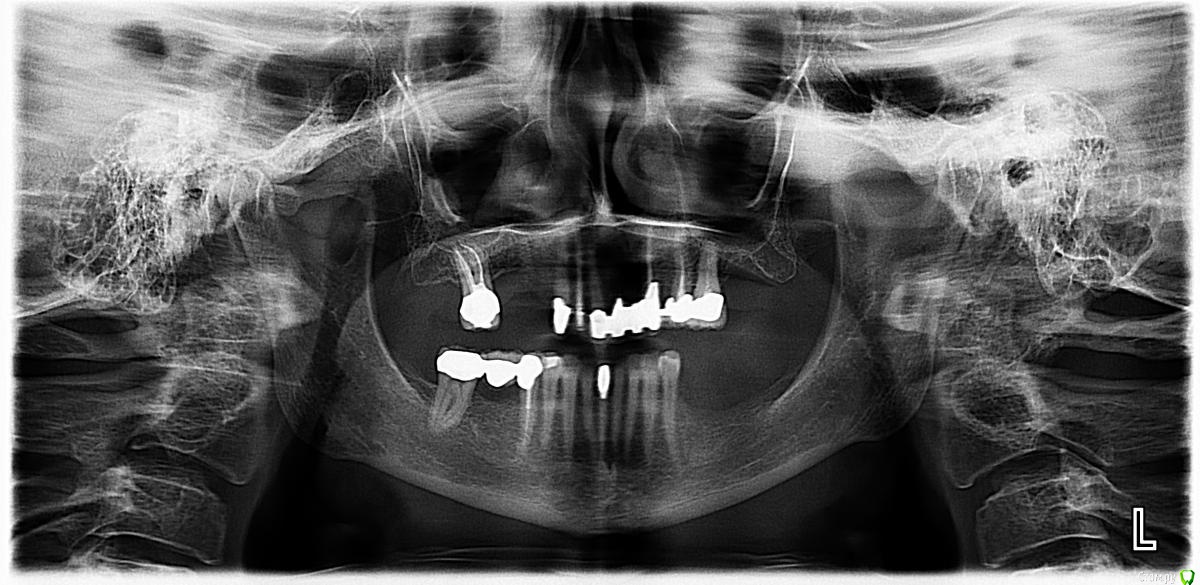

Dirina12 Опубликовано 20 июня, 2017 Автор Поделиться Опубликовано 20 июня, 2017 Эта проблема уже давно. Началось с того что под коронкой заболел зуб. Там был мост и поэтому врач переделал канал через коронку. Болт не ушла. Была такая тянущая боль, как жжёт. Локализации боли не было, болела вся сторона. На снимке ничего не показывало, тогда врач предположил что это средний зуб , распилил мост и удалил зуб. Болт никуда не ушла. И вот 16 июня мне опять открыли зуб и прочистили каналы. Но вот уже 4 й день а зуб болит. Без таблеток не могу( анальгин). Что делать? Может снять коронку и там будет кариес? Может ли кариес давать болт если нерв удалён.? Удалить зуб? Ну уже и так удалили один зуб зря. Первый снимок это уже до удаления среднего зуба. Второй снимок после. Вот тот последний слева ( на снимке) болит. 1 Ссылка на комментарий